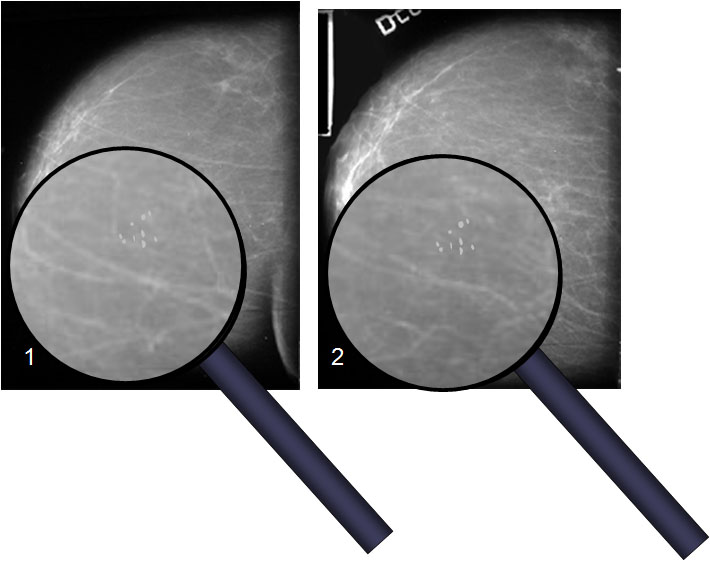

SIGNO DEL TATUAJE

Las microcalcificaciones dérmicas vistas en mamografía mantienen una relación fija entre ellas en proyecciones similares, como un tatuaje en la piel, a diferencia de las microcalcificaciones parenquimatosas, cuya relación no se mantiene.

Arriba: esquema de realización de la mamografía en posición cráneo-caudal. Abajo a la izquierda: mama vista de frente sobre la plataforma del mamógrafo. Simulación de calcificaciones dérmicas (flecha naranja) y calcificaciones parenquimatosas (flecha azul). Abajo a la derecha: con la compresión, las calcificaciones parenquimatosas cambian su relación entre sí mientras que las calcificaciones dérmicas la mantienen.